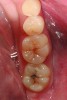

A 48-year-old patient presented with an old, failing Class I alloy restoration and showed recurrent decay on the lower molars (Figure 9). After the existing alloy was removed, the remaining tooth structure was evaluated. It was determined that despite the significant extent of caries present, it would be possible to perform a minimally invasive procedure using an injectable composite resin and an RMGI (Figure 10).

After removing the infected dentinal layer, a caries-detection stain was used to determine if further tooth removal would be necessary. On removal of all infected dentin, a chlorhexidine gluconate swab (CAVITY CLEANSER™ 2% Chlorhexidine Digluconate, BISCO, Inc.) was used to remove any surface bacteria on the prepared site. Next, a polyacrylic acid scrub was performed for 20 seconds to condition the dentin surface. An RMGI (GC Fuji II LC) was sculpted and light-cured to cover the affected and unaffected dentin.4,13,18,19 After the RMGI liner was fully cured, a micropreparation diamond bur (830RM.FG.009, Komet USA) was used to refine the internal form of the preparation. Marginal beveling to a 45° taper was completed along the cavosurface of the final tooth preparations.15